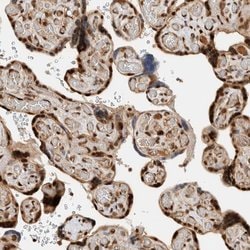

Invitrogen™ ZNF521 Polyclonal Antibody

Brand: Invitrogen™ PA554898

| Immunohistochemistry (Paraffin) | |

| Recombinant protein corresponding to Human ZNF521. Recombinant protein control fragment (Product #RP-93654). | |